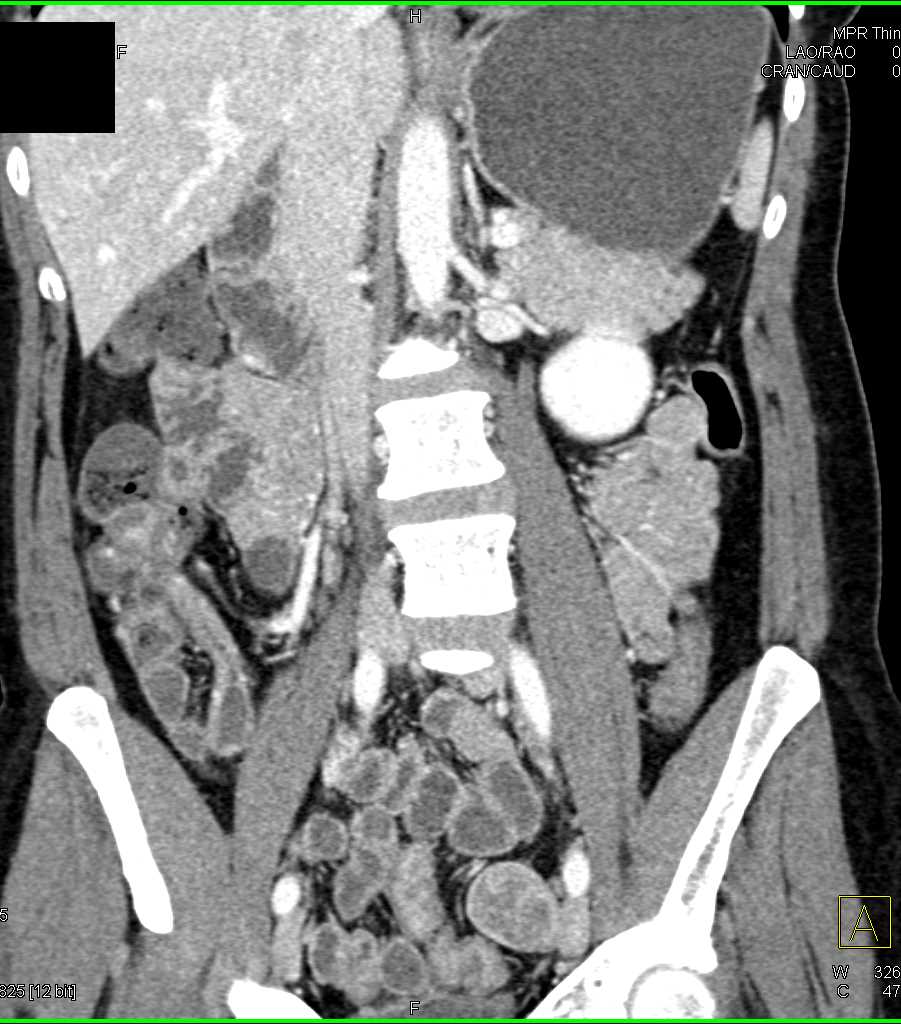

Crohns Disease Terminal Ileum